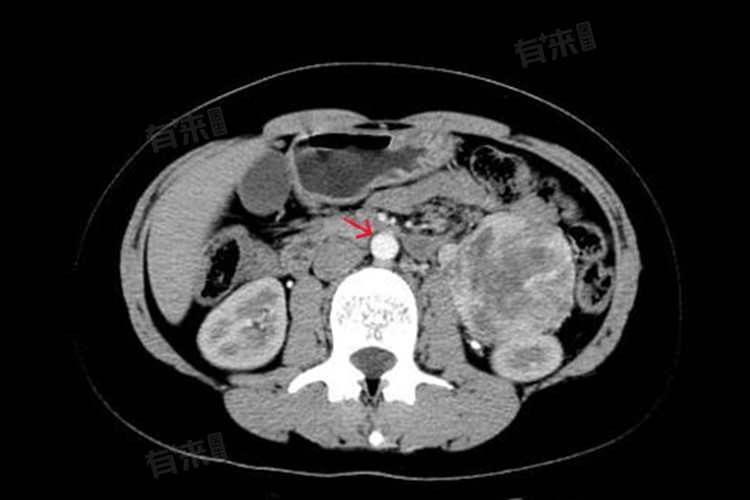

- 针对腹膜后淋巴结肿大的诊断,通常需要进行影像学检查,如超声波检查、CT扫描或MRI成像,以评估淋巴结的大小、形态和位置。此外,医生还可能建议进行活检,即从肿大的淋巴结中取出一小部分组织进行显微镜下观察,以确定是否存在癌变或其他病变。